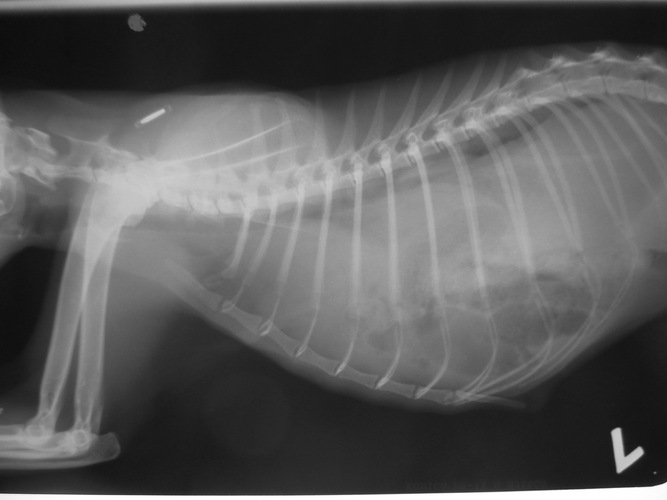

而這隻小黑帽,從外觀看起來沒甚麼外傷,但異常的喘,我趕快帶她前往樂生,當天下午醫生立刻打給我說,小黑帽很不妙!片子一照發現她出過車禍,很大的撞擊導致他的內臟全部往胸腔擠壓,所以牠才會異常的喘,這樣的症狀必須開刀,不開致死率百分百,但更麻煩的是小黑帽過瘦,牠目前才1.3公斤,加上有嚴重的流鼻涕和發燒症狀,所以沒辦法立刻施以手術,怕她承受不了,醫生建議先治療牠的流鼻涕和發燒,等到痊癒了且體重有增加了點,才會開刀。

10月1日入院經過所有檢查,確定有.橫膈赫尼亞症,導致牠呼吸急促

,但由於小黑帽約4個月大,體重過輕,到院時體重只有1.3公斤,醫生不敢貿然開刀,只好先用藥物舒緩牠的呼吸急促,醫生說先把小黑帽的其他疾病先給穩住後再來開刀會比較保險,所以小黑帽的住院天數會預估的長一點

照片3是手術前 照片6是手術後動物近況說明: 小黑帽18號回家,還蠻緊張的,沒有像在醫院那麼穩定,會哈氣,19號有穩定些,慢動作的接近他,就不會呼我了,我有用浴巾包住抱著她幫他測了體重是1.8公斤,目前以皇家幼貓當主食,然後每天會再加一餐【貝克牛磺酸錠磨成粉+THOMAS LABS 湯瑪士離氨酸 拌日本AIXIA《MiawMiaw》金妙喵(肽添加-肉狀餐罐)給他吃,所以他目前會吃到4餐,他目前的食慾都很好,喝水量都有超過150CC,他身上黴菌的部分已有好轉35%,想說等她再胖一點,皮膚狀況好一些再進行送養部分,我有在自己的臉書上寫他的一些生活狀況,請朋友分享讓認養進度可以快一點